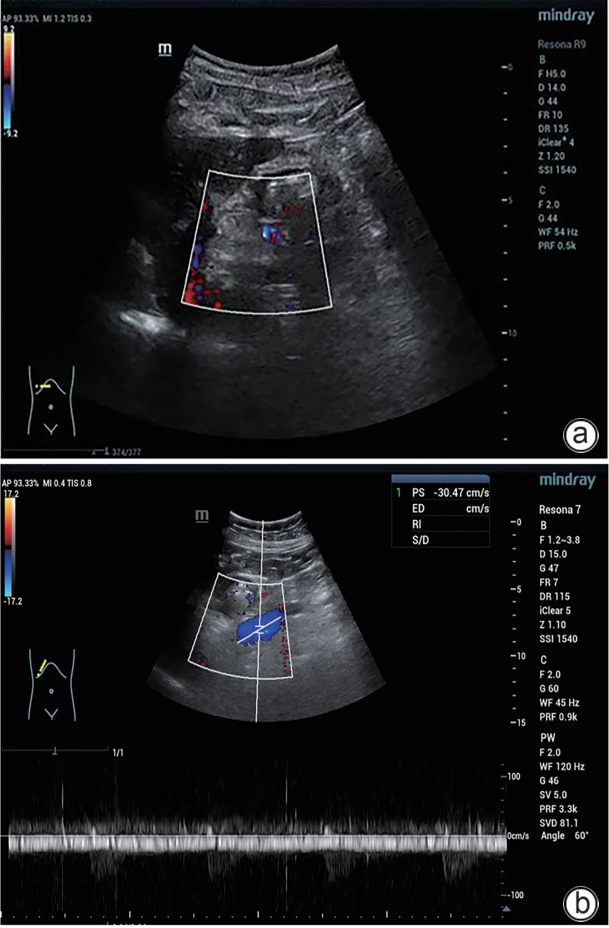

Large spontaneous splenorenal shunt embolization combined with anticoagulant therapy in treatment of portal vein thrombosis: A case report

Ju HUANG, Xiaoze WANG, Xuefeng LUO, Li YANG

2025, 41(8): 1639-1642. DOI: 10.12449/JCH250825

Abstract(504) HTML (172) PDF (3328KB)(67)

Abstract:

Portal vein thrombosis (PVT) is a common and severe complication in patients with liver cirrhosis, and alterations in portal hemodynamics are closely associated with the development of PVT. The presence of large spontaneous splenorenal shunt (SSRS) may lead to reductions in portal vein perfusion and blood flow velocity, which may compromise the anticoagulant effect on PVT. This article reports the treatment strategies of SSRS embolization combined with anticoagulant therapy that help to achieve complete recanalization of the portal vein; however, high-quality clinical studies are still needed to further validate and support the effectiveness of this strategy.